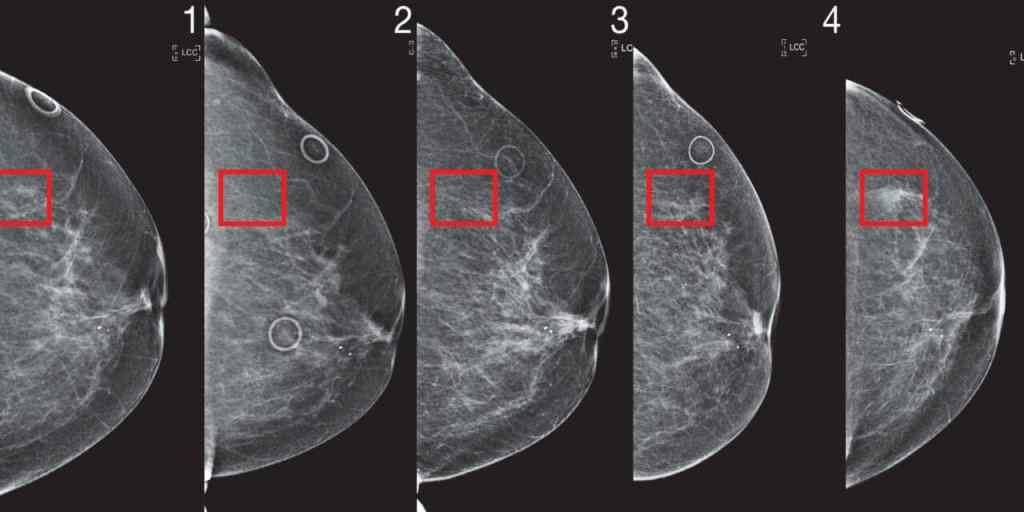

-read more->Perhitungan Diameter Kanker Payudara Menggunakan Metode Thresholding Otsu Pada Modalitas Mammography

Kanker payudara (carcinoma mammae) adalah salah satu jenis kanker yang paling umum terjadi pada wanita di seluruh dunia. Deteksi dini dan karakterisasi tumor payudara sangat penting untuk penanganan yang efektif dan tingkat kelangsungan hidup yang lebih baik. Citra mammography adalah alat penting dalam deteksi dini kanker payudara. Dalam penelitian ini, akan dijelaskan bagaimana metode thresholding Otsu digunakan untuk mengidentifikasi diameter kanker payudara pada citra mammography.